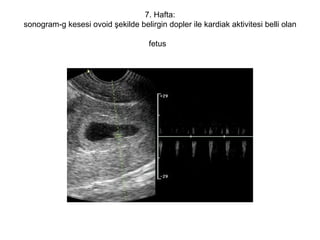

7. Hafta: Koryonik tabaka desidua ile yapışır ve plasentayı oluşturmaya başlar.Embriyo uzunluğu (CRL) 9-14 mm arasındadır  Embriyo bu dönemde sagittal planda bir üçgene benzer.Koronal planda ise silindir şeklinde görülür.  Ekstremiteler çok kısa olarak görülebilir. Kranyumda önden arkaya doğru hemisferler,diensefalon (ilerideki 3. ventrikül),mezensefalon (ilerideki aquaductus Sylvii) ve rombensefalon (ilerideki 4.ventrikül) oluşmuştur  Bu haftada başın hemen altında büyük,parlak ve hareket halindeki kalp görülür. Dakikadaki atım sayısı 130'dan 160'a yükselmiştir,ancak kalbin anatomik ayrıntıları çok zor ayırt edilir.İntestinal traktusta, umbilikal kordonun abdominal insersiyonunda ekojenite artışı ve kalınlaşma ile birlikte fizyolojik barsak herniasyonunun ilk belirtileri oluşur.

7. Hafta: sonogram-g kesesi ovoid şekilde belirgin dopler ile kardiak aktivitesi belli olan fetus

7. Hafta: sonogram-gkesesi ovoid şekilde belirgin dopler ile kardiak aktivitesi belli olan fetus